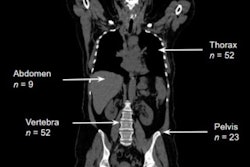

Pediatric lung MRI holds great potential as a radiation-free alternative to CT, offering superior soft-tissue contrast and functional imaging capabilities, according to award-winning research. Continued technological advances in MRI may further enhance its role in the comprehensive assessment of pediatric thoracic diseases.

Thoracic MRI has become viable for many pathologies, offering high sensitivity and specificity in several conditions. The indications can be broadly divided into lung parenchymal, mediastinal, and chest wall pathologies, with its diagnostic utility being particularly significant in children due to its radiation-free nature.

Techniques such as undersampling k-space or employing specialized k-space sampling strategies, including periodically rotated overlapping parallel lines with enhanced reconstruction (PROPELLER or BLADE), are effective in minimizing respiratory motion artifacts and improving image quality in challenging cases. Figures courtesy of Dr. Emre Ruhat Avci et al and presented at ECR 2025.

“Historically limited by challenges such as low lung proton density and air-tissue interface, advancements in MRI technology have significantly enhanced its utility,” they commented. “MRI is now sensitive for detecting and characterizing solid lung lesions, infiltrative disorders, respiratory mechanics, ventilation, perfusion, and mediastinal pathologies.”

Overall, it is important to understand the role of lung MRI and indications in pediatric patients, learn the MRI sequences commonly used in lung imaging, and identify the limitations of lung MRI and apply artifact-reducing techniques to improve image quality, the Izmir team emphasized.